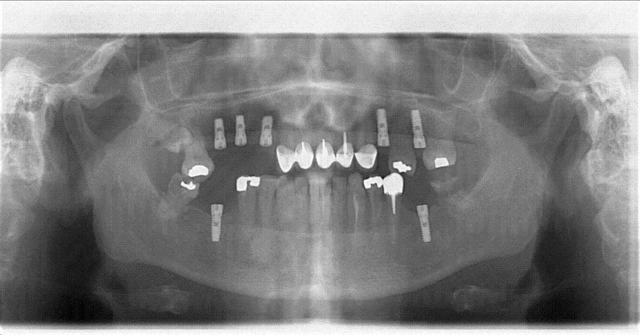

un nouveau patient m'annonce avoir fait poser des implants a l'etranger.donc pano;reconnaissez vous cette marque?

Bien sûr pas de passeport implantaire, pas de wax up, mi même de guide...encore les que là ils ont pas l'air d'être trop mal posé...en pinaillant on pourrait dire trop étroits pour les secteurs molaires...mais bon avec une pano on peut pas se rendre compte du volume osseux dispo...

En pinaillant un peu on pourrait surtout dire reprise de carie, proximité radiculaire des implants, manque d'espace prothétique en haut à gauche, trop d'espace en bas à droite, sagesse incluse....

si, moi ça m'interesse de savoir quel est le type d'implant mais avec un pano c'est pas facile alors envois une rétro numérisée :)